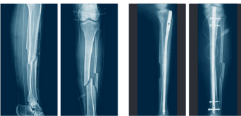

A compound injury is a general term for a bone fracture that pierces through the skin. In Paul George’s instance, it was the fracture of his entire lower leg; the tibia, and the fibula. The tibia is the larger, more dense bone in the front that supports the body’s weight and is designed for mobility. The fibula is the smaller bone in the back that is used as a stabilizer for the ankle and other muscles.

A compound injury is especially worrying since the bone breaks through the skin. It makes the risk for an infection much higher and requires immediate attention to both mend the bone and close the wound.

The surgical process began with the insertion of a titanium rod. The rod was designed to stabilize the tibia and fibula to ensure proper alignment during the healing process. After the rod was placed, the doctors had to manage the open wound. They focused on cleaning and closing the wound to prevent any infection from accessing the leg. Although the injury was terrifying, the immediate medical response and treatment helped tremendously in Paul George’s recovery.